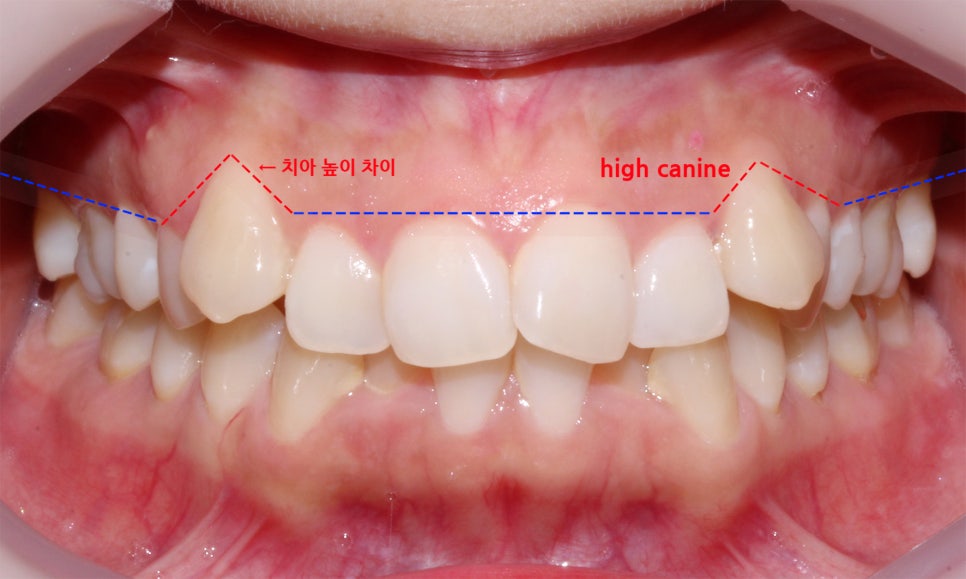

위의 Case는 역삼역치과의 송곳니덧니 증례로

정면 구내사진을 확인해보면 덧니의 전형적인

증상인 'high canine' 를 확인할 수 있습니다.

high canine란 위처럼 송곳니가 정상적인 치열에서부터

위쪽으로 멀리 튕겨져나간 것처럼 맹출된 모습을 말하며

이러한 경우에는 대부분 어금니까지

교정장치를 부착하는 전체교정을 통해

치열을 바로잡을 수 있습니다.

이러한 high canine는 기준이 되는 송곳니의

위치가 그다지 좋지 않기 때문에 억지로

전치부 부분교정을 하는 것보다

치아가 배열될 수 있는 충분한 공간을 확보한 후

전체교정으로 치열을 가지런하게 만드는 것이 중요합니다.